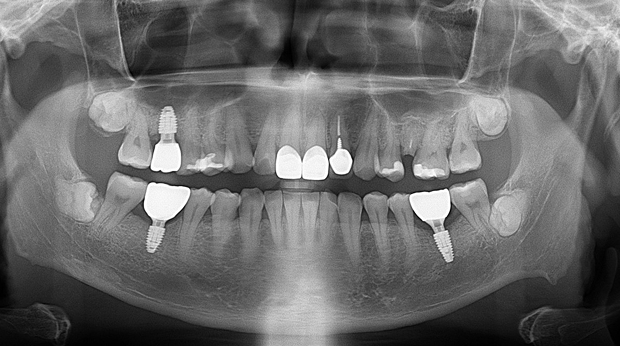

고난도 수술 진료

임플란트와 사랑니 발치는 외과적 시술로 잇몸을 절개하는 외과적 시술은

짧으면 짧을 수록 시술 후 붓기와 통증이 최소화됩니다.

치과의사 경력 14년차 구강외과 전문의가 빠르고 안전하게, 아프지 않게 수술해 드립니다.

치과경력 14년차 구강외과 전문의

연세대학교 치과대학 구강외과 임상 조교수